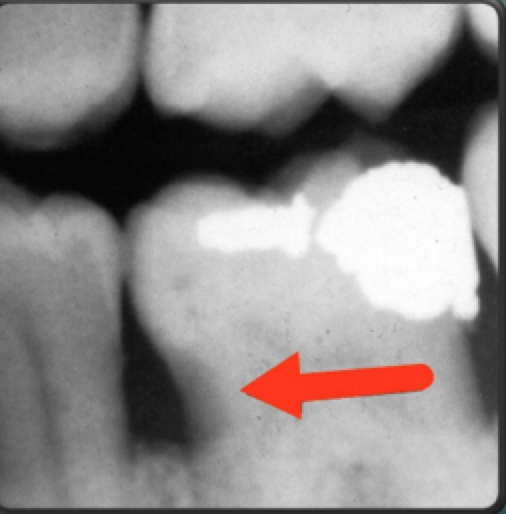

4-cervical burnout

4-between CEJ & alveolar crest

diffuse radiolucency

ill-defined borders

presence of edge of root

clinical evaluation

cervical burnout